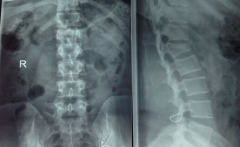

节日拥抱太激烈 居然出现腰椎骨折

多年老友相见,不少人都是热情拥抱。然而我们要提醒的是,拥抱适度即可,切不可用力过大,以免出现腰椎骨折,尤其是老年人更是需要适度拥抱。这不,近期新闻媒体就报道一则...

2015-05-02查看详情